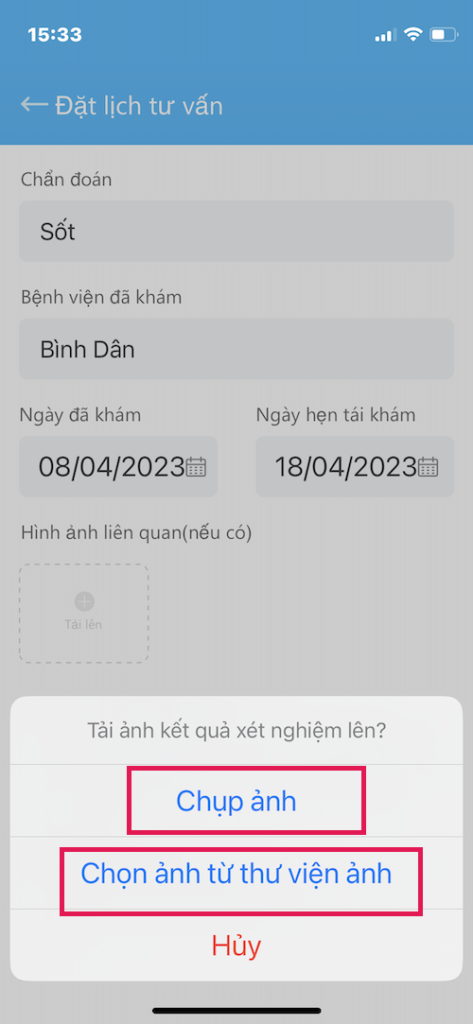

KHAI BÁO THÔNG TIN (tiếp theo)

Quan trọng nhất: trong Khai báo thông tin

- (8) TẢI HÌNH TOA THUỐC, GIẤY XUẤT VIỆN lên đây hoặc các hình ảnh vết thương, kết quả xét nghiệm,… Cung cấp cho Bác sĩ thông tin rất quan trọng để Bác sĩ điều trị cho Bạn tốt nhất.

- Chọn hình từ thư viện ảnh

- Hoặc chụp hình từ camera của điện thoại

- Có thể chọn nhiều ảnh cùng lúc

- Tối đa 10 hình